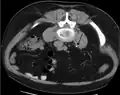

Otherwise a noncontrast helical CT scan with 5 millimeters (0.2 in) sections is the diagnostic method to use to detect kidney stones and confirm the diagnosis of kidney stone disease.[16][57][61][66][7] Near all stones are detectable on CT scans with the exception of those composed of certain drug residues in the urine,[59] such as from indinavir.

Measurement of a 5.6 mm large kidney stone in soft tissue versus skeletal CT window.